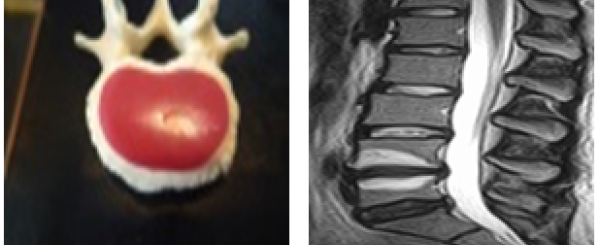

Billeder:

Typisk endepladeskade med hul; resultatet er Modic Type 1 forandringer, som ses som hvide pletter i rygknoglen

Der er forsket meget i Modic forandringer de seneste 10 år (1). Nu er det dokumenteret, at Modic forandringer er udtryk for en ødelagt endeplade og at endepladen i mange tilfælde ødelægges, når der opstår en discusprolaps fra den nærtliggende discus (se min næstsidste blog). Hvis endepladen ødelægges mister den samtidigt sin vigtigste egenskab: At udgøre en svært gennemtrængelig membran mellem discus og rygknogle (vertebra). Det er den manglende tæthed, som resulterer i væskeophobning/hvide pletter i rygknoglen betegnet Modic forandringer, og det er på den måde at der skabes risiko for inflammation, lokal vævsskade, øgede smerter og angreb af bakterier.